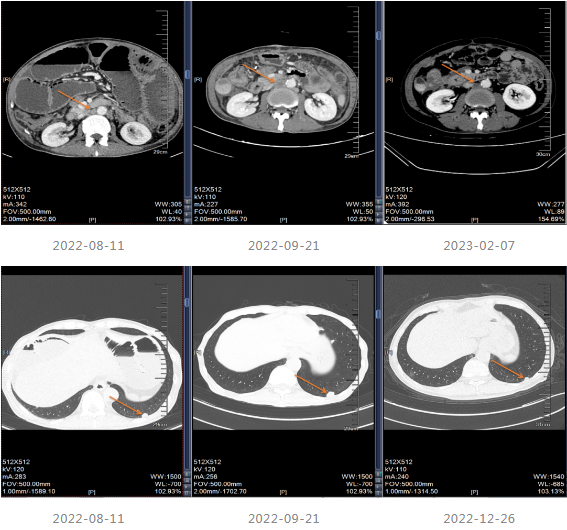

2021-12-20至2022-03-21更改化疗方案,采用“贝伐单抗+FOLFOX6方案”进行治疗。

2022-04至2022-07采用“贝伐珠单抗联合卡培他滨”维持治疗4周期,维持治疗期间患者渐感腹胀伴消瘦。

202-08出现肠梗阻,内科治疗效果不佳。

2022-08-29至武汉同济医院行小肠造瘘术。

患者出现肠梗阻,考虑病情PD,因此2022-10-06至今采用“斯鲁利单抗(200mg q3w)+呋喹替尼(4mg/d,口服,服3周停1周)”进行治疗,治疗过程中患者一般情况良好,体重增加。